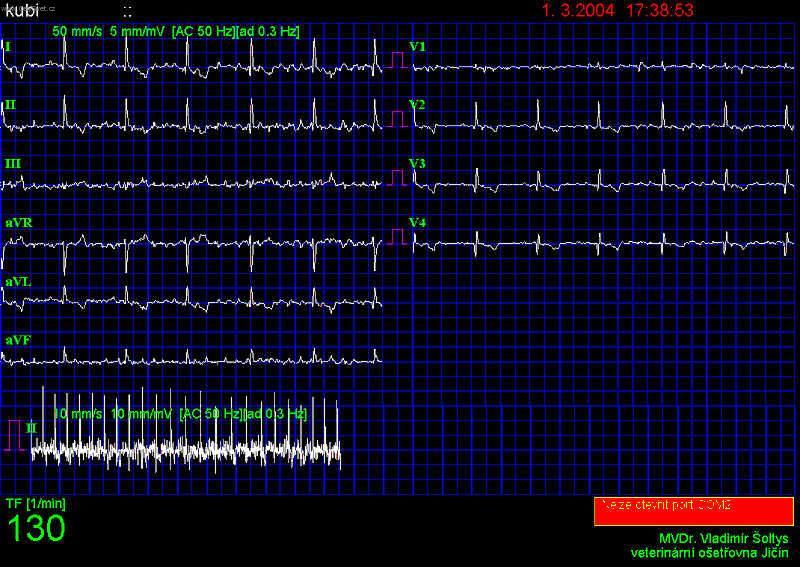

Foto: Fibrilace síní